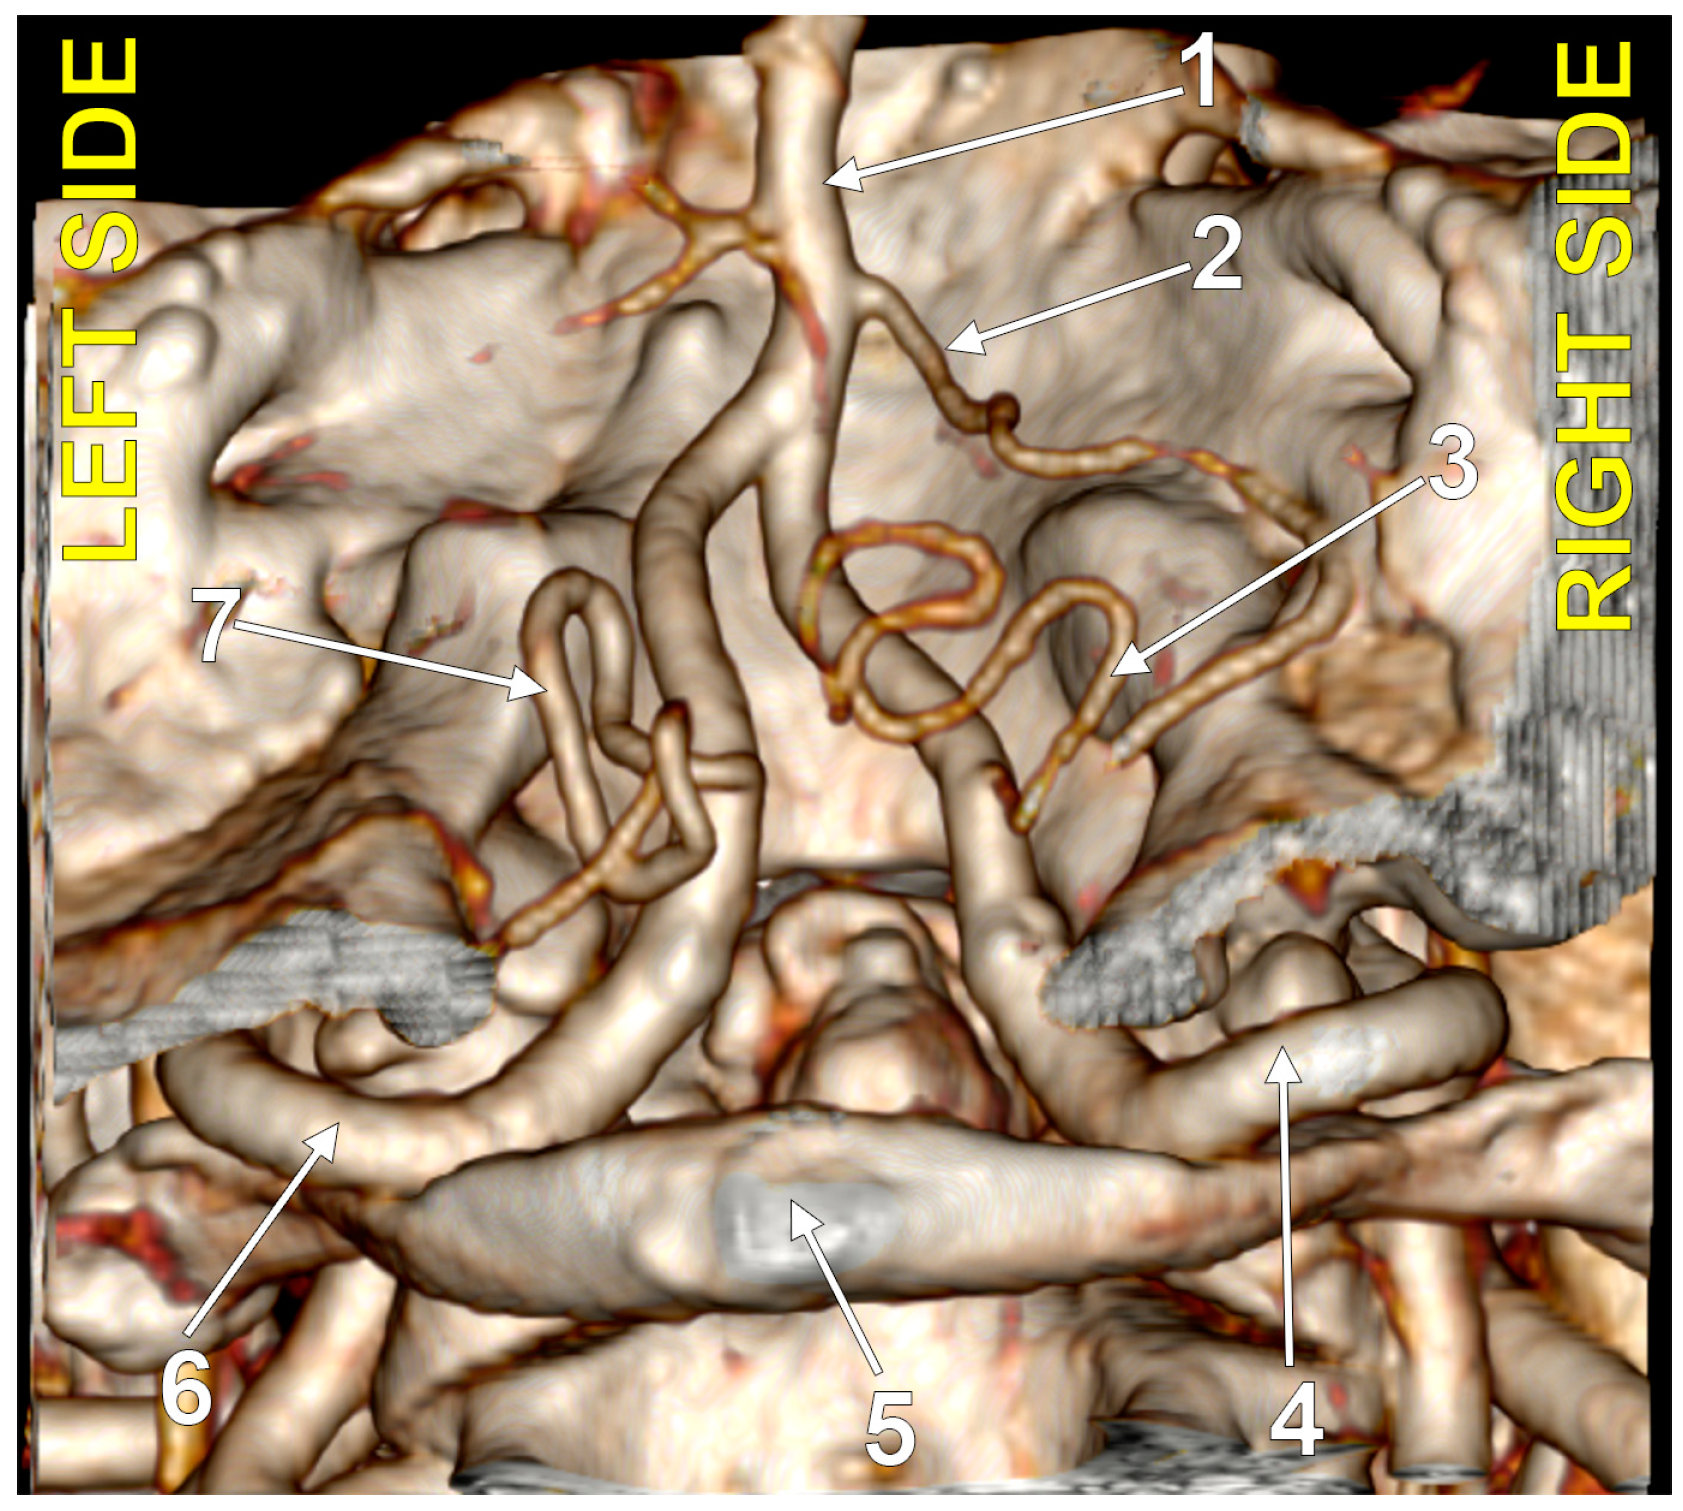

4.1. Typical PICA

4.2. Absent PICA

4.3. Extradural Origin of the PICA